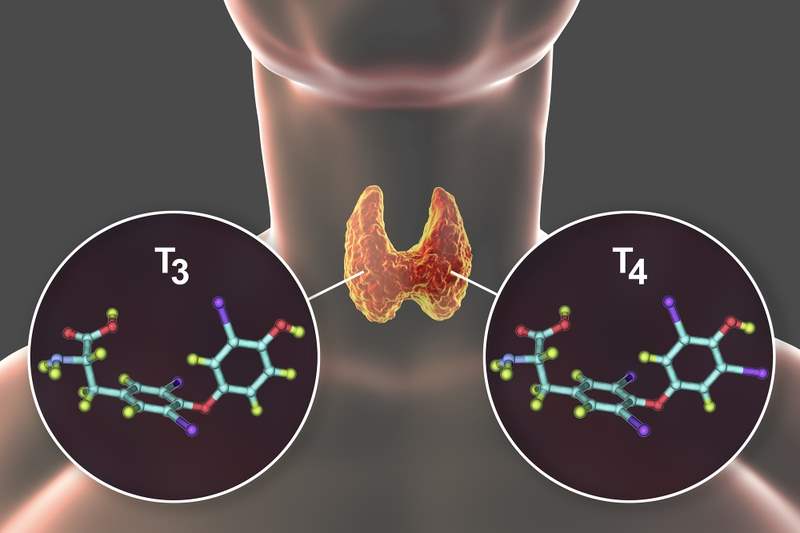

Triiodothyronine, thường gọi là T3, là một hormone tuyến giáp giữ vai trò quan trọng trong việc điều khiển tốc độ trao đổi chất và hoạt động của nhiều cơ quan. T3 chứa ba nguyên tử i-ốt, và chính cấu trúc này giúp nó trở thành dạng hormone tuyến giáp có hoạt tính mạnh nhất. So với T4 (thyroxine), T3 có khả năng tác động lên tế bào mạnh hơn khoảng 3–4 lần, vì vậy nó là “hormone điều khiển” chính trong các hoạt động chuyển hóa của cơ thể.

Cơ thể không sản xuất T3 theo một nguồn duy nhất. Tuyến giáp chỉ tiết ra 10–20% lượng T3, còn lại 80–90% được tạo ra từ T4 trong các mô như gan, não và cơ thông qua enzyme deiodinase. Cơ chế này đã được mô tả chi tiết trong nghiên cứu sinh lý học kinh điển của Bianco và cộng sự (2002), qua đó cho thấy mỗi loại deiodinase (D1, D2, D3) có vai trò riêng: D1 tham gia chuyển đổi T4 → T3 trong máu, D2 tạo T3 ngay tại mô cần thiết (như não), còn D3 bất hoạt hormone để tránh dư thừa.